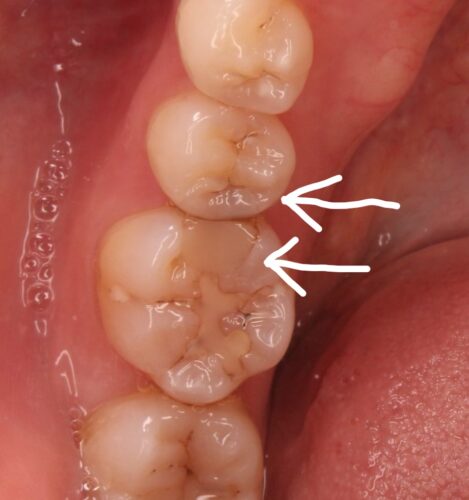

左下臼歯部の2次虫歯をセラミックで治療したケースです。

この方は、インビザラインで歯列矯正を行った後の虫歯治療です。

今回のケースは、詰め物の下に虫歯が残っていたため、患者さんのご希望もあり、セラミックでの治療を行いました。